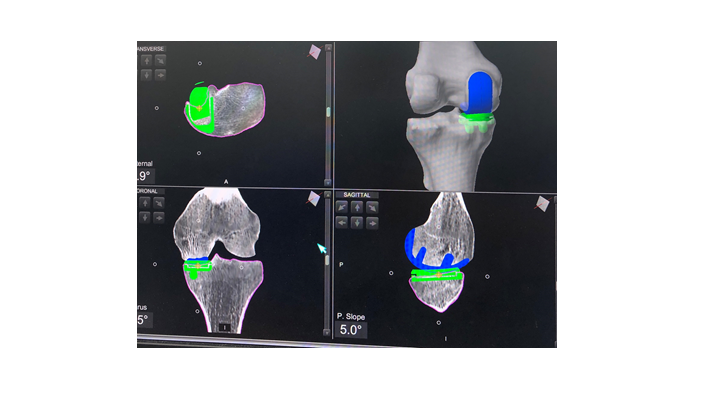

בשלב הראשון, מבוצע צילום CT של המפרק הפגוע. הצילום מוזן אל תכנת המחשב ובעזרתו מבצע האורתופד המנתח את התכנון הניתוחי. הלכה למעשה, התכנון המקדים מאפשר לאורתופד המנתח לקבל תמונה מלאה ומדויקת של מצבהמפרק ולתכנן את מהלך הניתוח עוד לפני ביצועו, לרבות סוג המשתל שיוכנס. כאמור, הניתוח מתבצע תחת הרדמה של חצי גוף בלבד. במהלך הניתוח, לאחר חשיפת המפרק, יוצבו קולטנים בשני צדדיו שמספקים תמונה תוך מפרקית מלאה. התכנה הממוחשבת תשווה בין מצב המפרק לבין התכנון הניתוחי ובעזרת הזרוע הרובוטית מבצע הרופא המנתח חיתוכים מדויקים של המפרק והחדרה של המפרק המלאכותי.

השימוש בטכנולוגיה הרובוטית מאפשר תכנון מקדים ומלא של מהלך הניתוח. בנוסף , השיטה המתקדמת מאפשרת פעולה כירורגית מצומצמת יותר והיא מקטינה את הסיכון לפגיעה ברקמות המצויות סביב המפרק. הדיוק האנטומי בחיתוכים המבוצעים על ידי הרובוט מצמצם את סיכוי לפגיעה רקמתית . בכל הנוגע להחדרה מדויקת של המשתל, הזרוע הרובוטית משפרת את סיכויי ההצלחה, ללא כל תלות במצב המפרק או באנטומיה האזורית. כל אלה מאפשרים שיקום מהיר יותר עם חזרה מהירה לפעילות, משפרים את שביעות הרצון מהפעולה הכירורגית ואת בטיחות הניתוח.כיצד מתבצע הליך השיקום לאחר הניתוחים הרובוטיים?